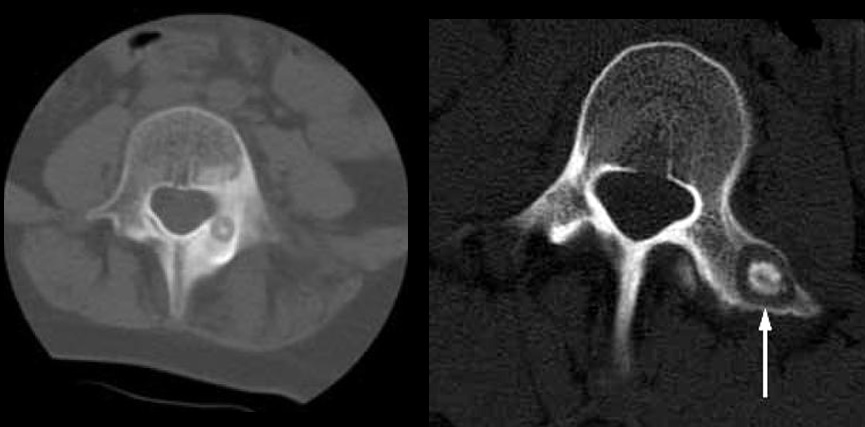

10

Q

Qual diagnóstico?

A

Lesão lítica na cortical espessada

dx: Osteoma osteóide

11

Nidus < 1,5

Nidus < 1,5 cm